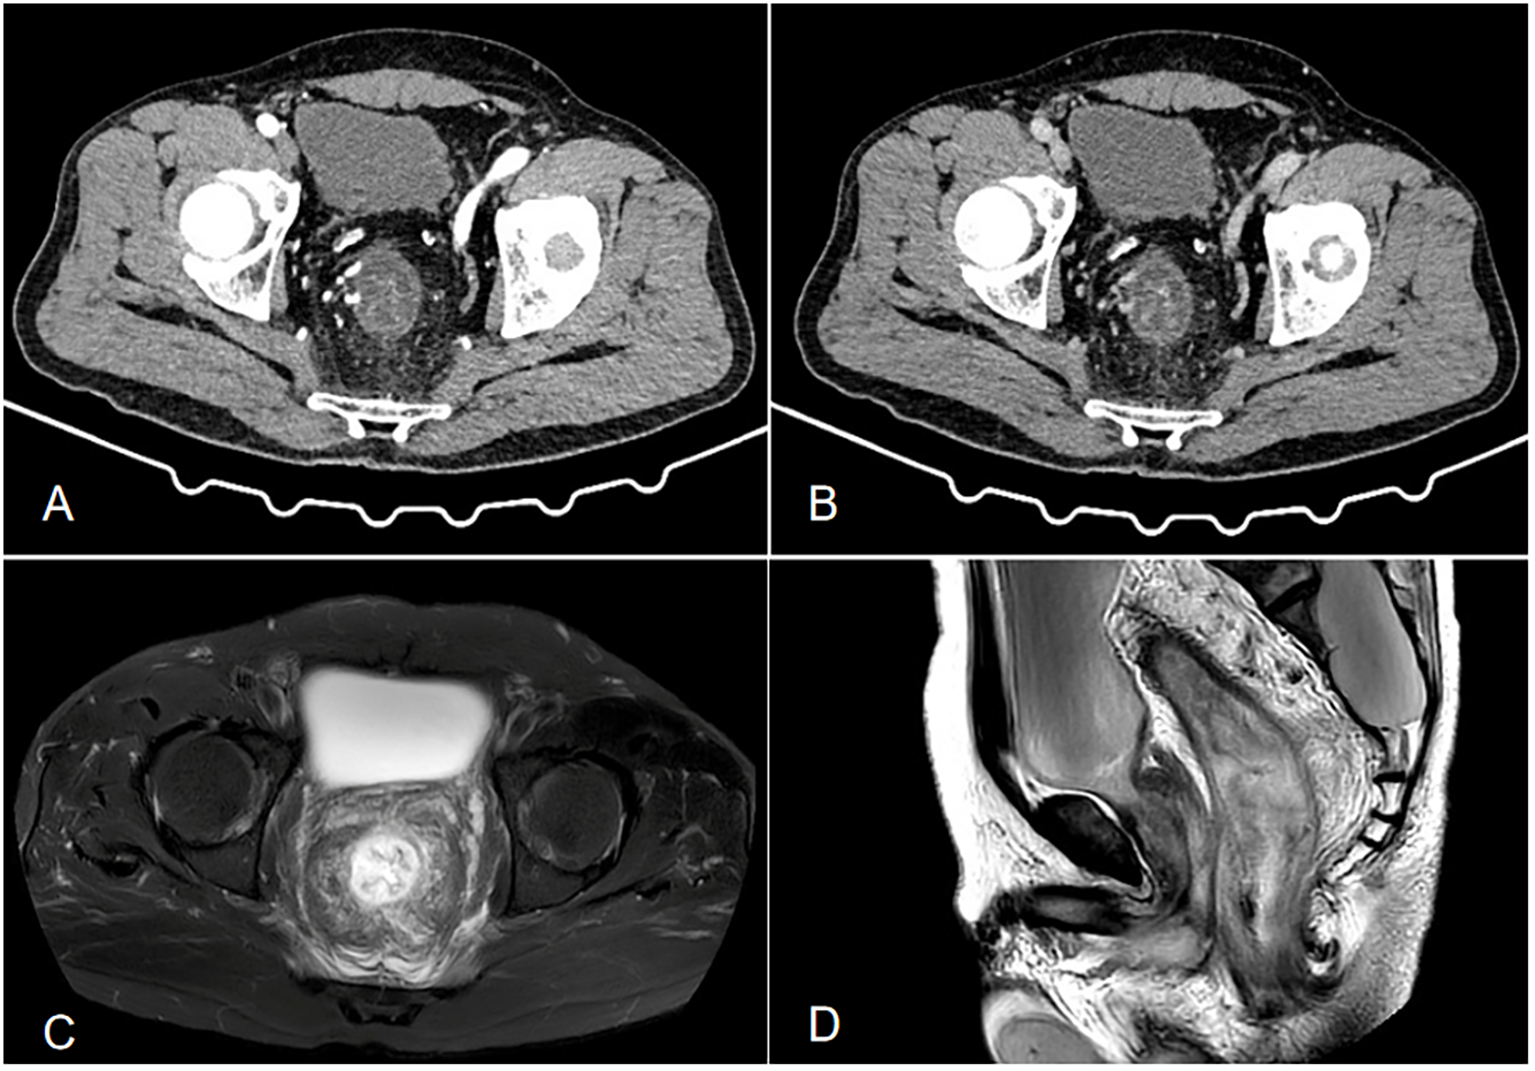

An initial blood test revealed white blood cell count (13.69×109/L) with 84.1% neutrophils. Liver function, renal function, coagulation, tumor markers, erythrocyte sedimentation rate, and autoantibodies were normal. Infectious workup (c-ANCA, p-ANCA, EBV, CMV, hepatitis viruses, syphilis, HIV) was negative. Fecal cultures and Clostridioides difficile tests were repeatedly negative. Contrast-enhanced abdominal CT (Figure 1) showed rectosigmoid wall thickening with submucosal edema, increased mesorectal vascularity, and partial large bowel obstruction. Enhanced pelvic MRI demonstrated segmental wall thickening of the rectum and sigmoid colon with marked blurring in the perirectal fat plane. Colonoscopy (Figure 2A) revealed mucosal edema and erythema from the rectum to the segment 20 cm from the anus, with the remaining colonic mucosa being normal. Pathological examination revealed chronic inflammation of the rectal mucosa with erosion, which is considered to be ulcerative proctitis. Mesalazine, steroid therapy and antibiotics were initially administered as treatment.

Figure 1

(A, B) Contrast-enhanced CT shows local wall thickening and heterogeneous enhancement of the sigmoid colon, with increased and thickened surrounding blood vessels, dilation and effusion of the proximal intestinal lumen, thickening of the distal rectosigmoid colon wall showing a layered change, and layered enhancement after enhancement. Its feeding artery is thickened, with exudation and fascia thickening seen around(a is the venous phase, and b is the arterial phase). (C, D) Enhanced pelvic MRI demonstrated segmental wall thickening of the rectum and sigmoid colon with marked blurring in the perirectal fat plane. (c is T2-weighted fat-suppressed sequence, and is Sagittal T2WI sequence).